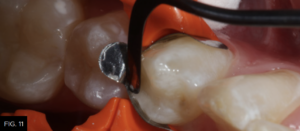

Using a unidose delivery, the first increment of composite resin (Evanesce, Clinician’s Choice) is placed into the proximal box of the preparation. A smooth ended composite placement instrument (Goldstein Flexithin Mini 4, HuFriedy) is used to adapt the restorative material to the inside of the sectional matrix and preparation. (FIG. 11)

The first increment of nano-enhanced composite (Evanesce, Clinician’s Choice) is placed using a composite placement instrument (Goldstein Flexithin Mini 4, HuFriedy).